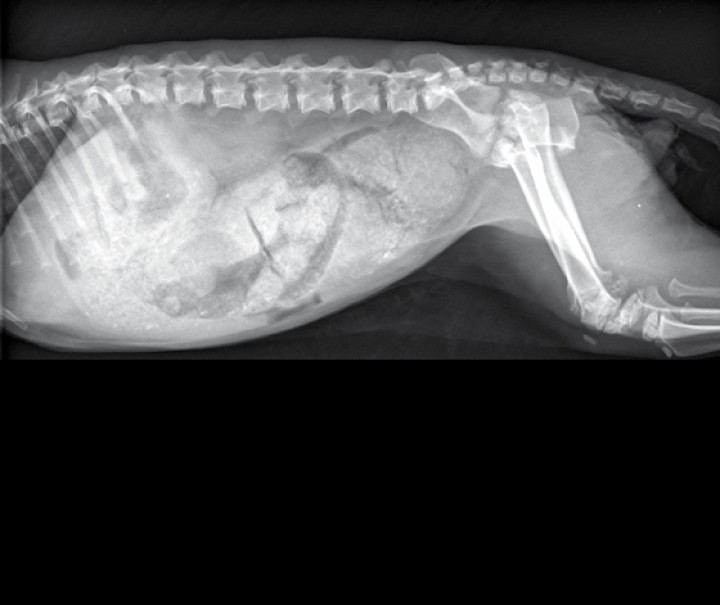

Se presenta en consulta un gato macho, entero, común Europeo, de 1 año de edad, con anorexia y vómitos de 3 días de evolución, además de estreñimiento y apatía desde el nacimiento. En la exploración física general se evidenció a la palpación dolor abdominal y contenido de consistencia compacta en abdomen caudal, ptialismo, retención de dientes deciduos, enanismo desproporcionado, baja condición corporal (2/5) y aumento de la persistencia del pliegue cutáneo. Las alteraciones observadas en la bioquímica sanguínea fueron hipertrigliceridemia (114 mg/dl; rango de referencia: 20-60 mg/dl), hipercolesterolemia (294 mg/dl; rango de referencia: 64-229 mg/dl), hiponatremia (145 mEq/l; rango de referencia: 149-163 mEq/l) e hipocalemia (3,3 mEq/l; rango de referencia: 4,10-5,40 mEq/l). En la hematología pudo observarse una leve leucocitosis debida a neutrofilia (15,31 x 103/µl; rango de referencia: 2,30-10,29 x 103/µl). Se realizaron radiografías de la cavidad abdominal en las proyecciones lateral derecha y ventrodorsal (Fig. 1).

<p>Radiografías de abdomen de un gato común Europeo de 1 año de edad. (<strong>A</strong>) Proyección lateral derecha. (<strong>B</strong>) Proyección ventrodorsal.</p>

Radiografías de abdomen de un gato común Europeo de 1 año de edad. (A) Proyección lateral derecha. (B) Proyección ventrodorsal.